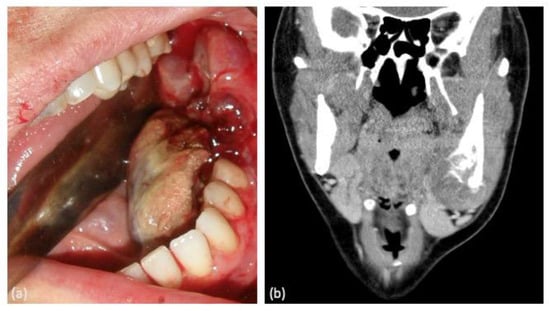

3.2. Pathological Characteristics of Tumor Lesions

| Case | Age | Sex | Medical History | Signs and Symptoms | Bone | Side |

|---|---|---|---|---|---|---|

| 1 | 51 | M | Pneumothorax at 26 years | -Sensation of nasal obstruction -Progressive proptosis -Diplopia | Maxilla | Left |

| 2 | 35 | F | None | Painful swelling | Maxilla | Left |

| 3 | 56 | F | Cavum cancer (T2N2M0) at 45 years. Treated with CTX and RTX | Painful swelling | Mandible (angle) | Right |

| 4 | 56 | F | None | Asymptomatic mass | Mandible (body and angle) | Right |

| 5 | 49 | F | Uterine myoma. Breast fibroadenoma | -Inferior dental nerve hypoesthesia -Painful swelling -Dental mobility of involved teeth | Mandible (body and angle) | Left |

| 6 | 47 | F | Maxillar cemento-ossifying fibroma at 42 years | Asymptomatic mass | Maxilla | Right |

| 7 | 10 | F | Retinoblastoma at 3 years. Treated with CTX and RTX. Right eye enucleation | Painful swelling | Maxilla | Right |

| 8 | 31 | F | Appendectomy at 21 years | -Painful swelling -Oral cavity bleeding | Mandible (body and angle) | Left |